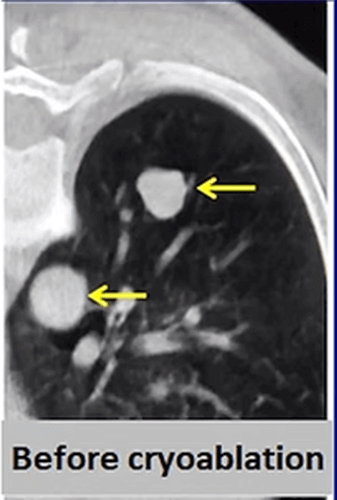

Cryoablation is the newest ablation method in the lung but it is more and more frequently applied for lung cancer. The most important advantages of cryoablation are that it is not painful, can be performed under local anesthesia, can be used in tumors close to the chest wall, the ablation area can be seen as an iceball and larger tumors (> 3cm) can be treated by increasing the number of needles.

In our patient who had a 4x2cm non small cell lung cancer, cryoablation was performed. After the procedure, the 3 and 6 months control CT images show progressive shrinkage of the tumor.

In the same patient, 2 metastases that grew after 2 years were cryoablated using 2 needles. Three months later, the control CT shows that both masses have shrunk and become a residue.